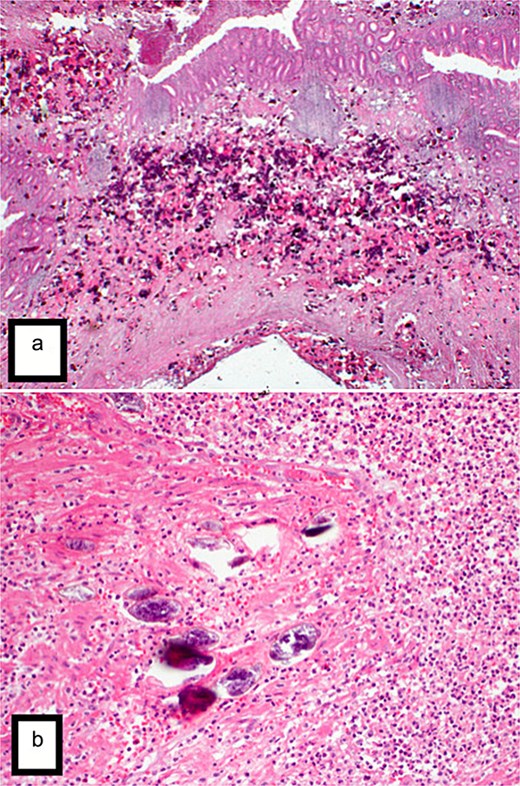

Final histopathological examination revealed the appendix show extensive transmural deposition of calcified Bilharizial ova on the background of acute suppurative appendicitis with periappendicitis (Fig. 3a and b).

(a) H&E stain (4×) revealed the appendix shows focal transmural deposition of calcified Bilharizial ova on the background of acute suppurative appendicitis with periappendicitis. (b) H&E stain (40×) revealed the appendix shows focal transmural deposition of calcified Bilharizial ova on the background of acute suppurative appendicitis with periappendicitis.